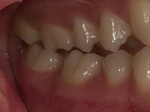

普通にかみ合わせた位置です。

雑音が無くなる咬み位置です。上の写真と比較すると、

雑音が無くなる位置はかなり前で咬んでいる事がわかります。